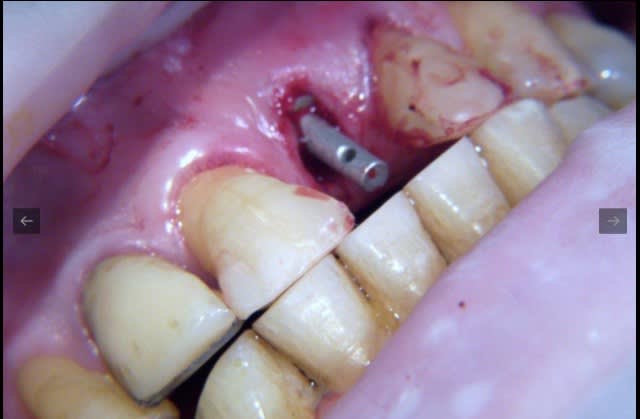

pour ceux que ça intéressent, une petite utilisation d'expansion de la paroi palatine, sur une avulsion d’incisive(racine fendue). toutes mes excuses pour la mauvaise qualité des photos.

voilà prothèse moyenne mais aucun souci